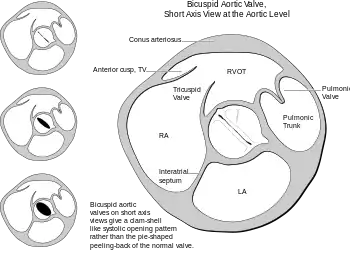

Heart bicuspid aortic valve anatomy.

Fusion of aortic valve leaflets occurs most commonly (≈80%) between the right coronary and left coronary leaflets (RL), which are the anterior leaflets of the aortic valve.[16][17] Fusion also occurs between the right coronary and noncoronary leaflets (RN, ≈17%), and least commonly between the noncoronary and left coronary leaflets (≈2%).[16][17] In comparison to other fusion patterns, RN leaflet fusion has a stronger association with future complications such as aortic valve regurgitation and stenosis.[18][19] However, all fusion patterns associate with a specific area or areas of dilated enlargement in either the root of the ascending aorta, the ascending aorta, or the transverse aortic arch.[16][17][18][20]

Bicuspid aortic valves may assume three different types of configuration:[24]

1. "Real" bicuspid valves with two symmetric leaflets

2. A tricuspid architecture with a fusion of two leaflets

3. A tricuspid architecture with a fusion of three leaflets